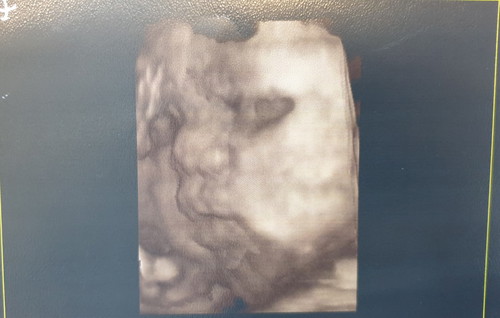

ตั้งท้องได้ 28+6 week น้ำหนักลูกในท้อง 1805 กรัมทุกคนคิดว่าน้องจั้มม้ำ ตัวโต น่าจะแข็งแรง แต่เราเป็นเบาหวานขณะตั้งครรภ์ น้องตัวโตกว่าเกณฑ์มาก เท่ากับอายุครรภ์ 32week ซึ่งใหญ่เกินไปสำหรับอายุน้อง หมอเลยให้ควบคุมอาหาร และควบคุมน้ำตาลโดยการฉีดอินซูลีน เพื่อควบคุมน้ำหนักน้องในท้อง ถ้ายังควบคุมไม่ได้ น้องอาจจะเสียชีวิตในท้อง เนื่องจากตัวโต ทำให้ขาดอ๊อกซิเจนได้ ต้องคอยคุม และคอยระวังจนถึงคลอด น้ำหนักตัวแม่ไม่ได้ขึ้นเยอะระหว่างท้อง แต่น้ำหนักและน้ำตาลนั้นลงที่น้องเกือบหมด แม่ๆที่กำลังตั้งครรภ์อย่าชะล่าใจนะคะ ดูแลตัวเองด้วย เพื่อตัวแม่และน้องเองนะคะ